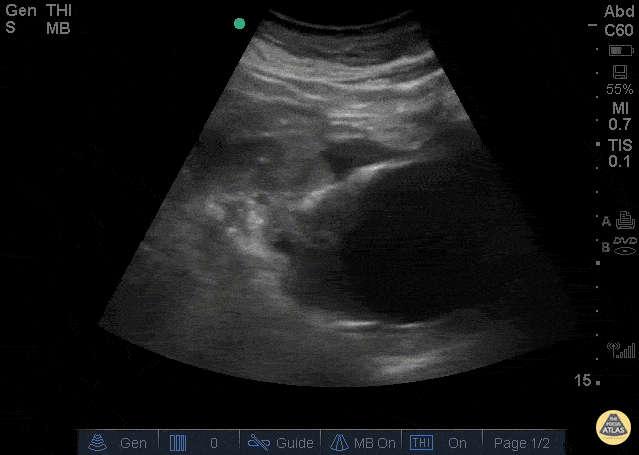

Aorta - Ruptured AAA

The clip above is from a patient who presented with abdominal pain and syncope. His vitals were notable for tachycardia and hypotension. The image demonstrates a very large abdominal aortic aneurysm with anterior free fluid suggestive of rupture. The patient was taken emergently to the operating room for endograft repair and did well. Jason Tanguay, DO